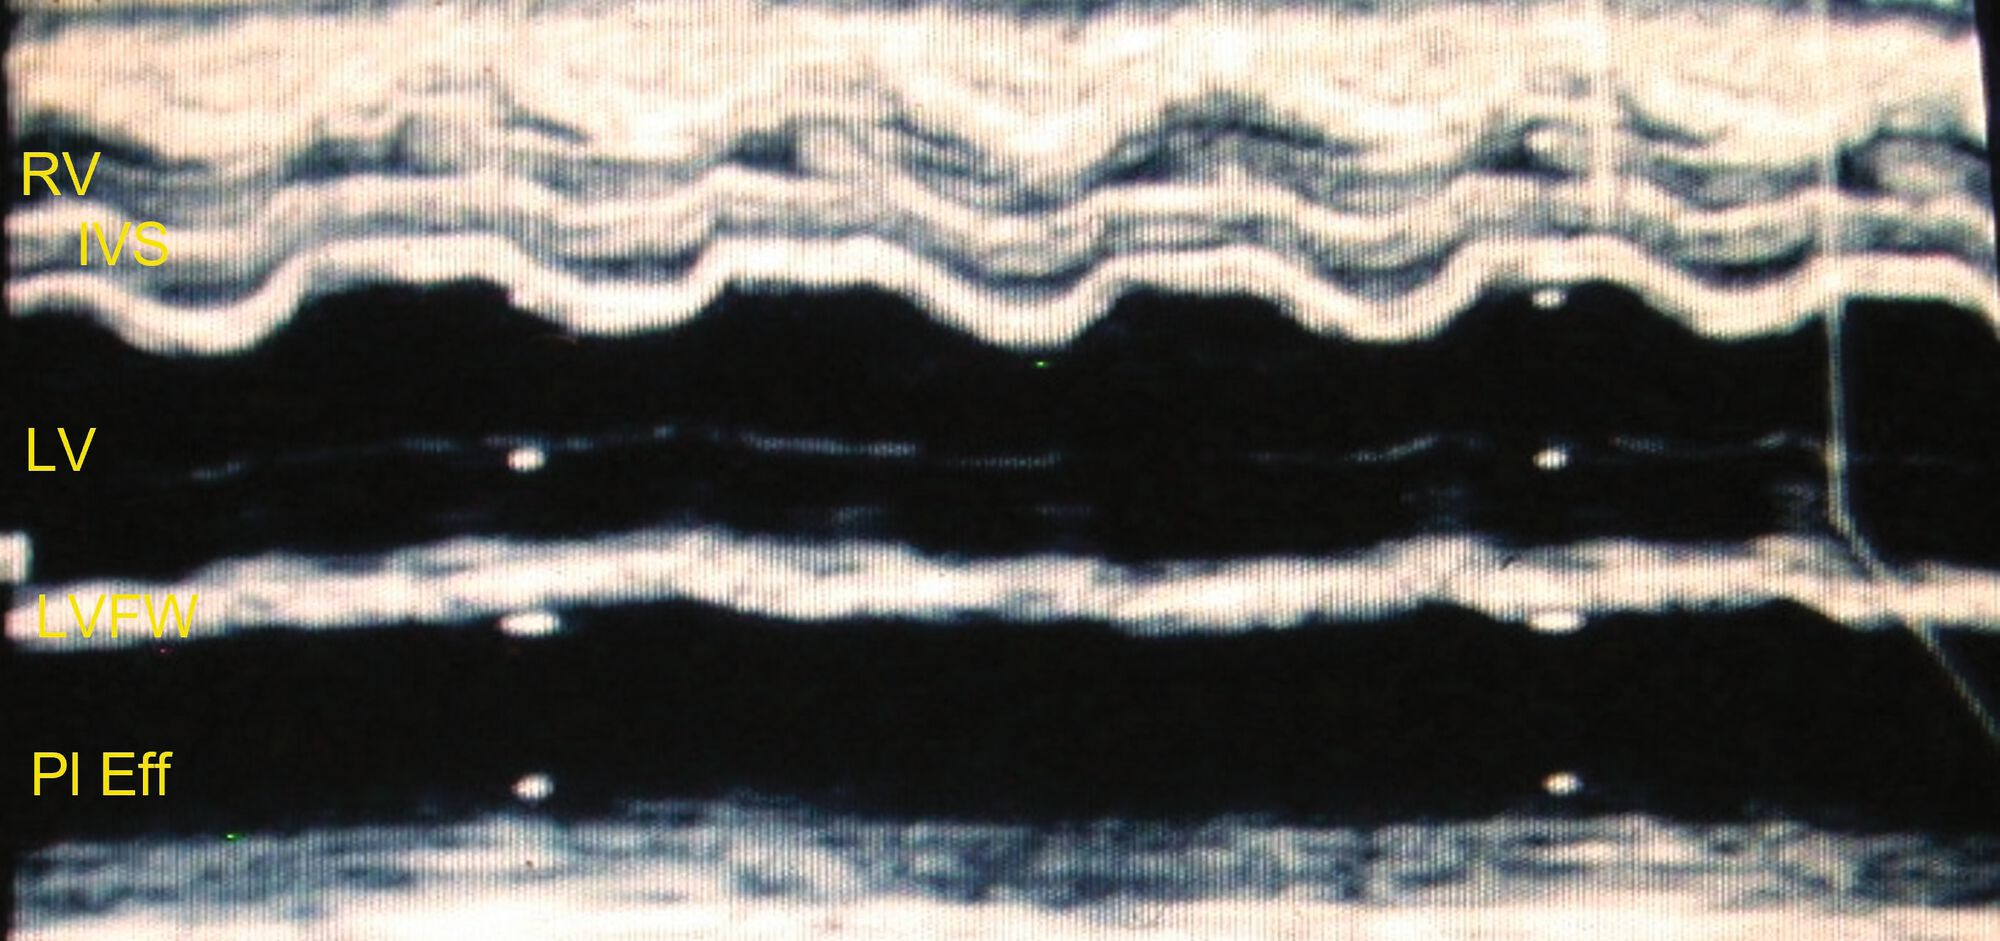

Vue en mode M du VG montrant une fonction systolique altérée chez le même chat que dans la Figure 6a

Figure 6b. Vue en mode M du VG montrant une fonction systolique altre chez le mme chat que dans la Figure 6a ; la fraction de raccourcissement tait faible et les mouvements de la paroi libre du ventricule droit sont apparemment bons. Catheryn Partington Joanna Dukes-McEwan